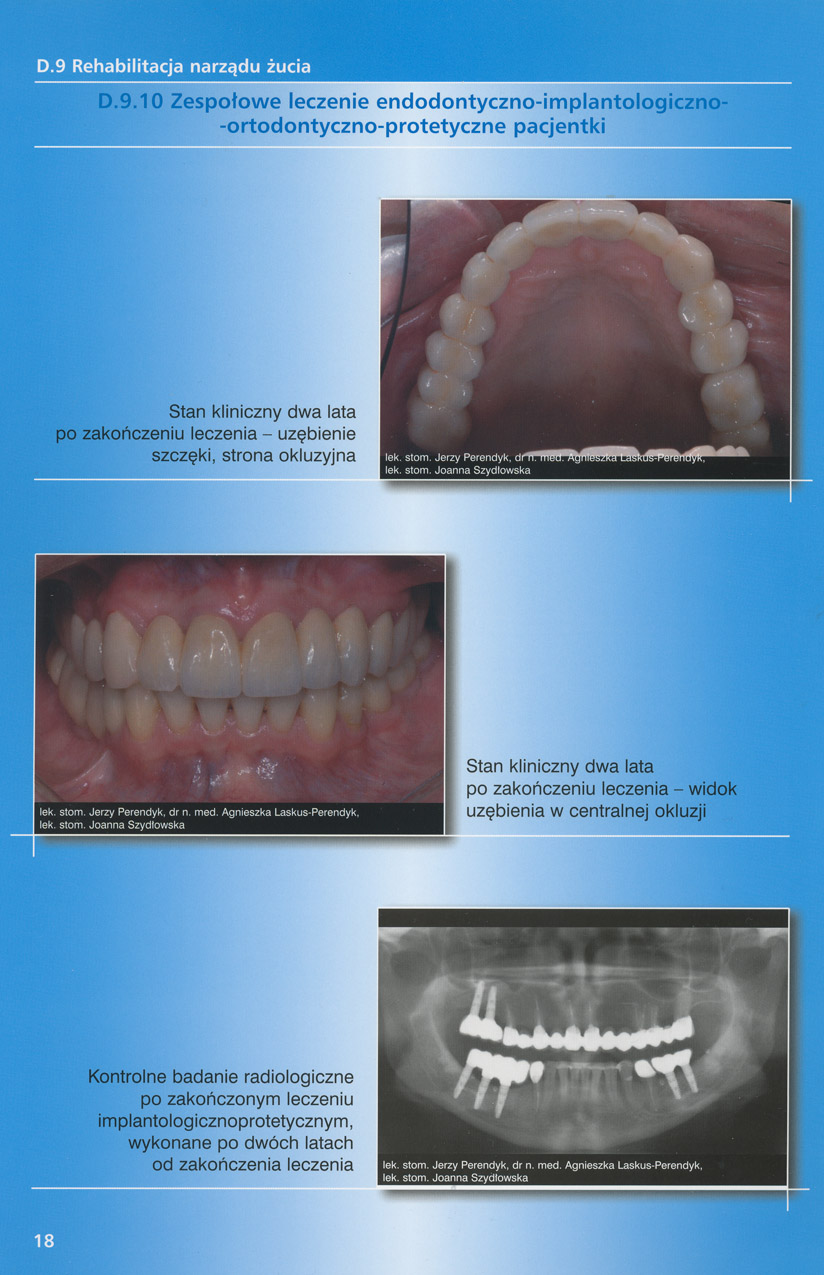

zobacz więcejGaleria przypadków klinicznych, obrazująca proces terapeutyczny od stanu wyjściowego aż do oddania ostatecznej pracy uzupełnienia brakującego uzębienia.